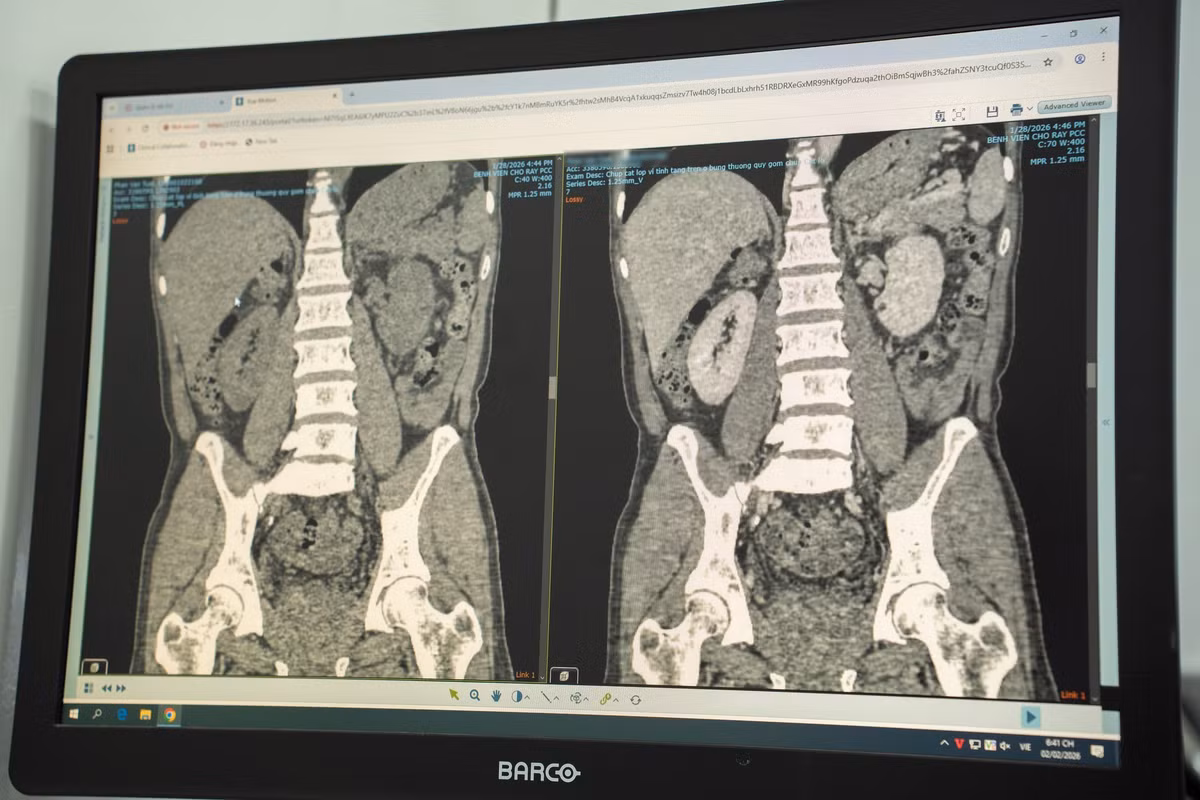

Khi tiến hành siêu âm kỹ hơn, ê-kíp phát hiện một dị vật cản quang xuyên trong nhu mô gan, chiều dài ước tính khoảng 6-7cm. Ngay sau đó, bệnh nhân được chỉ định chụp cắt lớp vi tính (CT scan) ổ bụng.

Kết quả cho thấy có một dị vật dạng que dài nằm hoàn toàn trong nhu mô gan, kèm theo ổ áp xe sâu. Trước nguy cơ biến chứng nặng nếu không điều trị kịp thời, ê-kíp khoa Nội tiêu hóa đã nhanh chóng hội chẩn cùng khoa Ngoại Gan Mật Tụy, thống nhất phương án phẫu thuật lấy dị vật, dẫn lưu ổ áp xe, kết hợp điều trị kháng sinh phù hợp.

Chia sẻ về sự phức tạp của ca bệnh này, ThS BS Trần Đình Quốc, Khoa Ngoại Gan Mật Tụy cho biết, ca phẫu thuật gặp nhiều khó khăn do ổ áp xe nằm sâu trong nhu mô gan, vị trí gần cơ hoành và các mạch máu lớn.

Ban đầu dự kiến sẽ tiến hành phẫu thuật nội soi cho bệnh nhân nhưng buộc phải chuyển phương pháp mổ để có thể tiếp cận an toàn, xử lý ổ áp xe và lấy dị vật. Thời gian phẫu thuật vì vậy cũng kéo dài gấp đôi so với các ca áp xe gan thông thường.